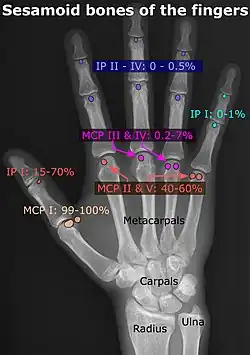

Prevalence, structure, and locations of sesamoid bones of the hand.[5][6]